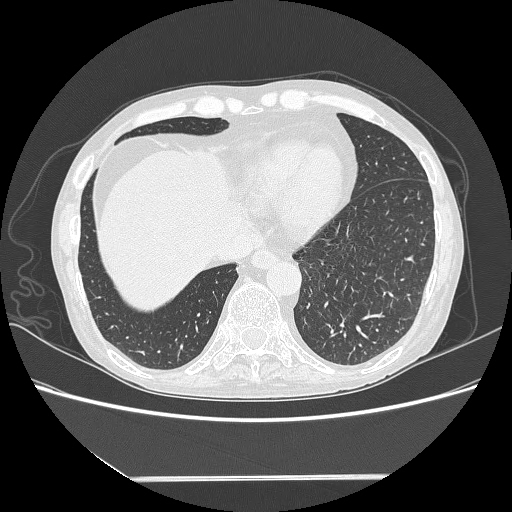

HRCT done on 17Mar16